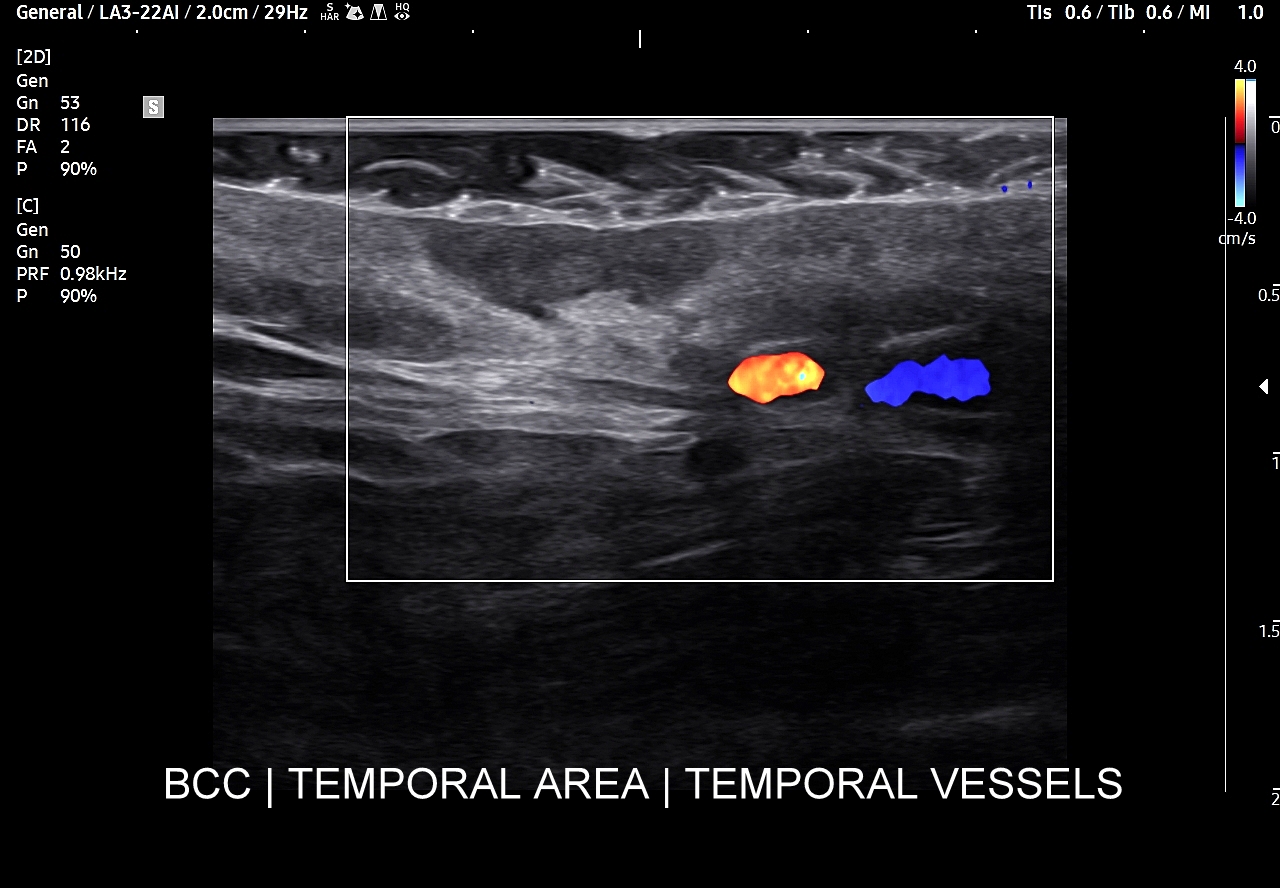

BCC jest nowotworem wywodzącym się z warstwy podstawnej naskórka. Przez długi czas naturalnego przebiegu sonograficznie obserwuje się jego ograniczenie do warstw naskórka i skóry właściwej. Struktura miąższu BCC w badaniu USG zwykle jest hypoechogenna i jednorodna. Wykrycie ewentualnych hyperechogennych mikro-plamek świadczy o zwiększonej inwazyjności raka podstawnokomórkowego. Jeśli chodzi o unaczynienie BCC to może być ono różne; obserwuje się zarówno guzki hypowaskularne, jak i bogatounaczynione. Zmiany bogatounaczynione oraz z obecnym tętniczym profilem przepływu niskooporowego będą miały tendencję do szybszego wzrostu. Niezależnie od powyższego czasami stwierdza się również odczyn zapalny w tkankach sąsiadujących z nowotworem.